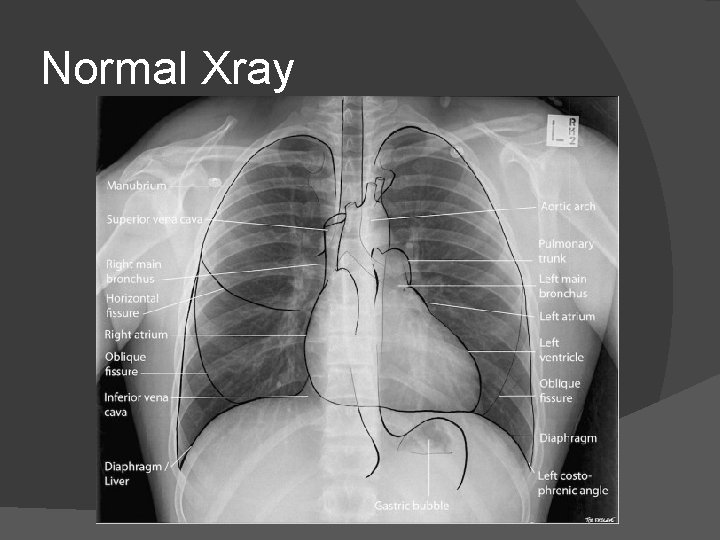

Normal Xray